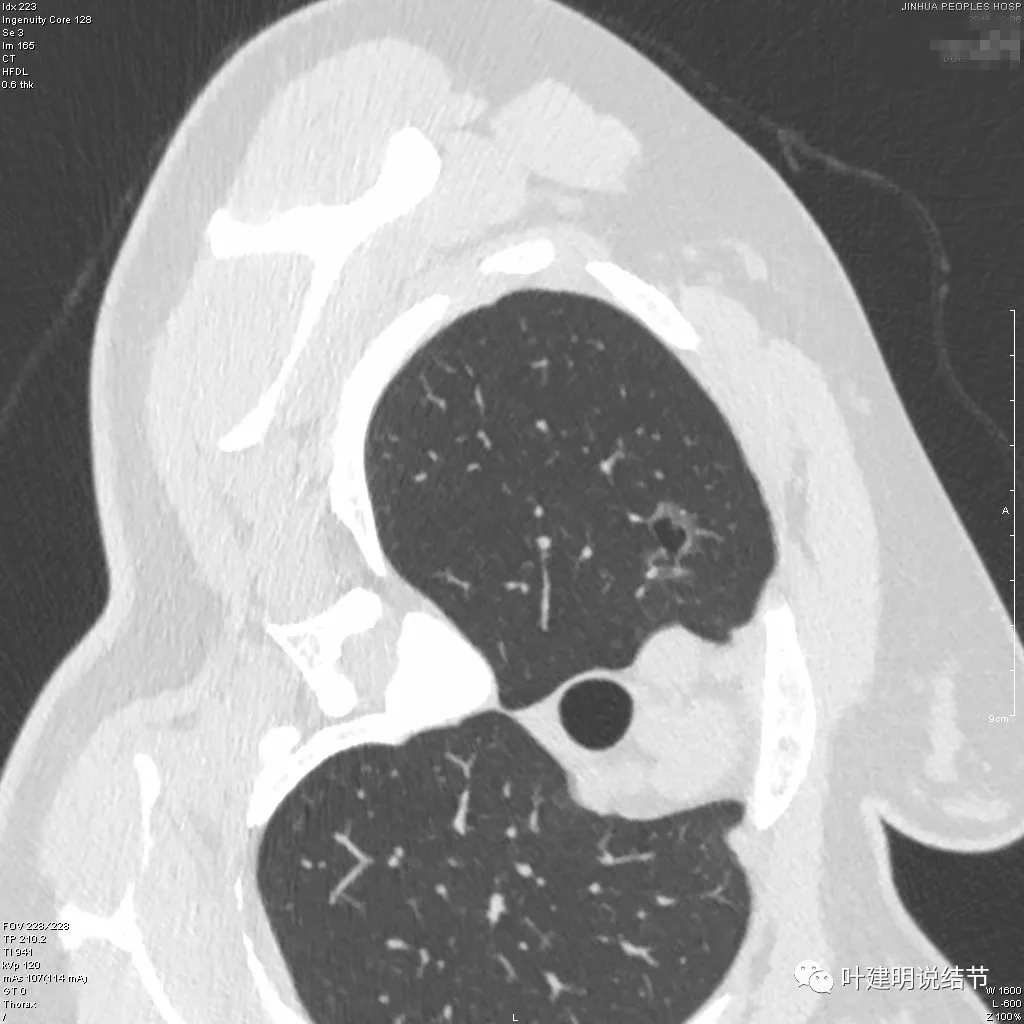

总结了囊腔型肺癌的特征才能一眼认出此类病变来。下面这些是前些年我曾经归纳的囊腔型肺癌的较为典型的例子:

这些都是我们已经经过手术病理证实的囊腔型肺癌,这是我几年前总结的囊腔型肺癌从影像上看有以下特点:(1)可以表现为磨玻璃密度,也可以表现为混合密度或实性密度;(2)病灶中间或偏心处有空泡或空腔,范围可大可小。空泡或空腔较大时就像厚壁空洞,当其壁含有边界与轮廓清楚的磨玻璃成分(鳞癌或结核的空洞为实性密度)时更加典型与容易判断;(3)典型时环形,漂亮的如戒指,即使边缘光滑也会是恶性;(4)当病灶含磨玻璃成分时,磨玻璃成分与周围正常肺组织界限一般清晰,当然也可显示为毛刺征或棘突征,特别是密度不纯或偏实性的时候;(5)当肿瘤在肺大泡基础上发生,可为实性成分,局部增厚突起。近年来又碰到许多囊腔型肺癌,我重新归类后觉得下面这几点更为重要与关键:(1)囊壁厚薄不均;(2)血管进入囊壁并穿行;(3)磨玻璃密度的轮廓与边界清以及实性密度的毛刺与胸膜牵拉。有这几条,若再加上随访过持续存在,概率就非常大。